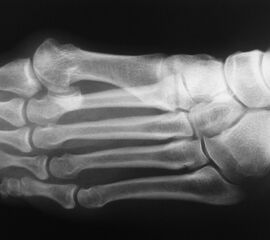

Röntgenaufnahme des Fußes (unter Belastung) in dorsoplantarem, seitlichen und schrägem Strahlengang (Abb. 1a-c).

Beurteilung des ersten Intermetatarsalwinkels (IMA), des Hallux valgus Winkels (HVA), des distalen (Distal Metatarsal Articular Angle, DMAA) und proximalen Gelenkflächenwinkels der Grundphalanx (Proximal Phalangeal Articular Angle, PPAA). Möglicherweise muss die Arthrodese des TMT-1-Gelenks mit weiteren distalen Eingriffen zur Korrektur des Gelenkwinkels kombiniert werden (z.B.: retrokapitale Osteotomie oder Grundphalanxosteotomie).

Zur Vollansicht bitte die Bilder anklicken.

Abbildung 1a

Abbildung 1b

Abbildung 1c